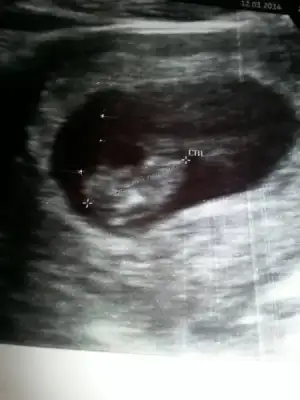

Gurbet ablam arkadasimin bebegi ALLA RIZASI ICIN BI BAKSAN KIZ MI ERKE MI? ustteki iki resim bugunku goruntuler en alttaki 6 hatalikken

Insallah erkektir, zeynepcim mutlaka haber vericem ama kizada benzettiler hayirlisi